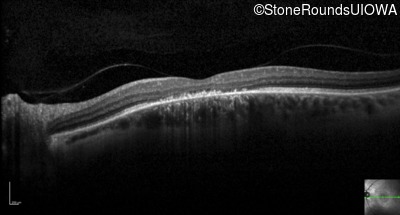

Optical Coherence Tomography - Right - 20/60 sc

Exemplar / OCT Stack